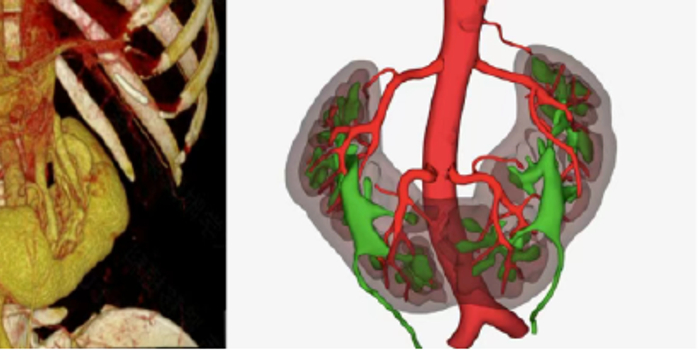

供者马蹄肾CT血管成像(CTA)及三维重建结构图

术前,肾移植团队利用高分辨CTA及三维重建技术,对供体的马蹄肾进行了毫米级的精准评估,清晰勾勒出异常走行的肾动脉、肾静脉及输尿管,特别是明确了相连的肾峡部血供及集合系统情况。本例供者的特点是峡部长度和厚度较大(长7cm,厚2cm),双肾血管复杂(双肾静动脉均为多支,且动脉距离较远),由于国内先前并无此类手术案例参考,国外也鲜有报道,肾移植科结合以往实施公民逝世后捐献马蹄肾手术经验,与相关学科反复模拟论证,制定了详尽的手术方案,为最大化保障供者安全及移植肾功能,最终决定采用腹腔镜下切取结构相对更优的左半侧肾脏,利用遗体捐献血管进行重建后再行肾移植的手术方案。